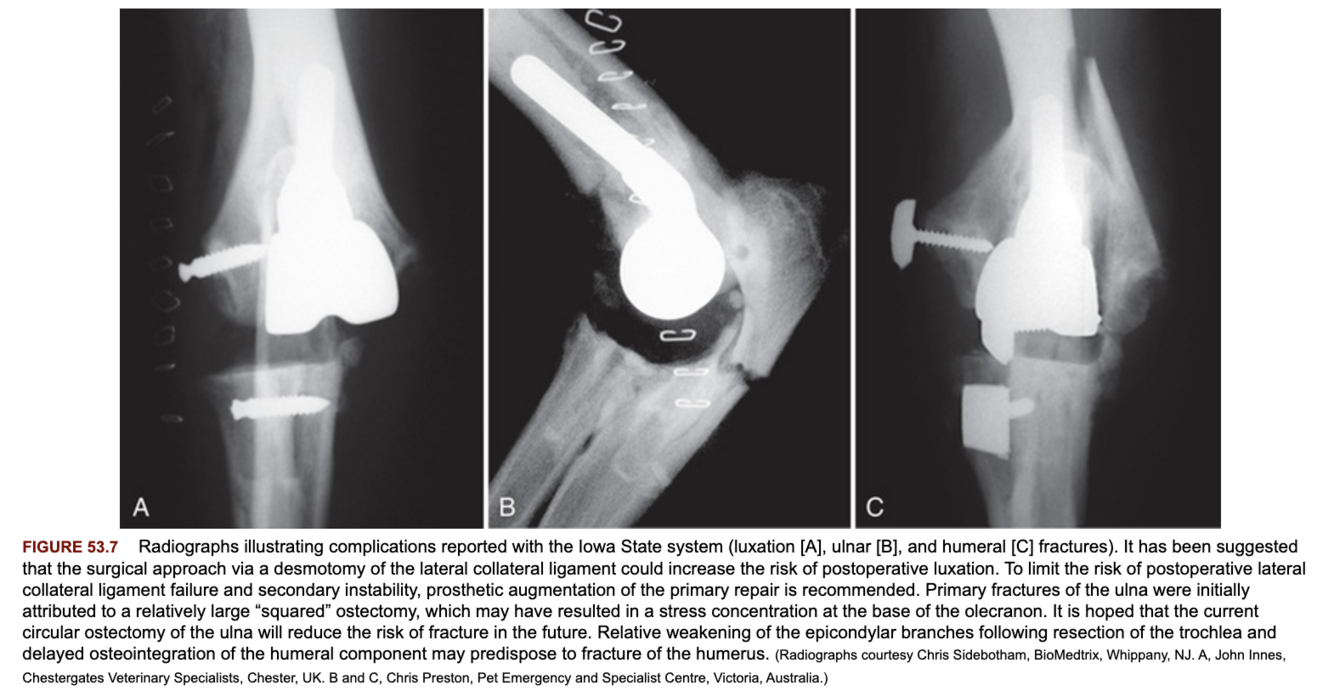

What are the primary complications associated with the Iowa State total elbow replacement system?

Elbow joint luxations and fractures of the ulna.